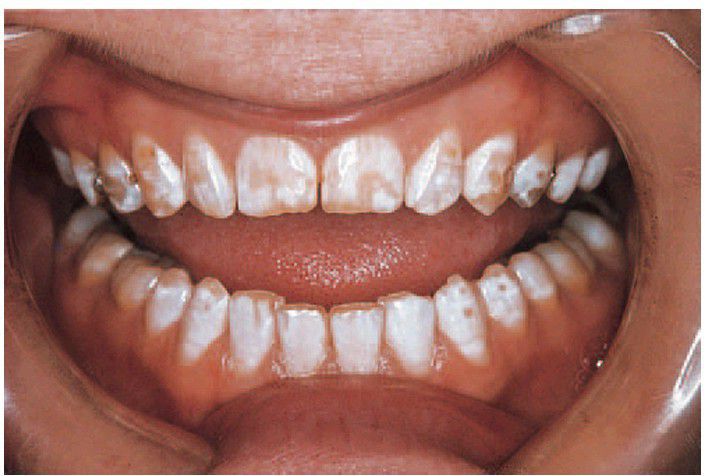

Flouride mottling

In this case, from an area of endemic fl uorosis, there is generalised opaque white mottling with patchy enamel hypoplasia. Note the resemblance to the hypomaturation type of amelogenesis imperfecta.